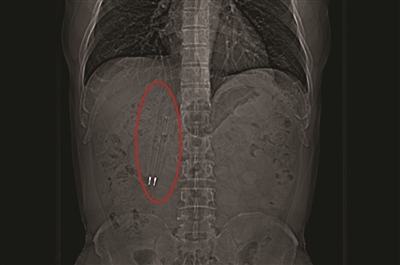

CT中能清晰看到亮闪闪的笔尖。

王先生体内的笔长约12厘米,位于十二指肠球降部。昆山中医院消化内科主任徐宏伟介绍说,这个笔从口中吞下,经过了食管、胃、幽门,到达了十二指肠,其中有一支笔的笔尖已经戳到了肠壁,由于十二指肠长度和一支笔的长度差不多,笔无法再向下滑。

王先生吞下去的这两支笔都是塑料的,从CT上看,还可以看到笔里的金属弹簧和金属笔尖在闪闪发光。

笔藏在肠道里长达36年未被发现,这是为什么呢?徐宏伟感慨道:“他真的是非常幸运。”因为,两支笔被吞下后,平行地进入了食管,进入到十二指肠后,也是一直跟肠道平行,因此,未对其身体造成很大的伤害。